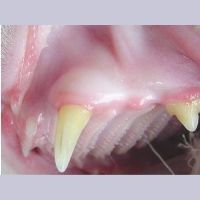

Image 7.12. Lymphocytic Plasmacytic

송곳니와 작은 어금니 주변의 염증

고양이과 Lymphocytic Plasmacytic 증후군